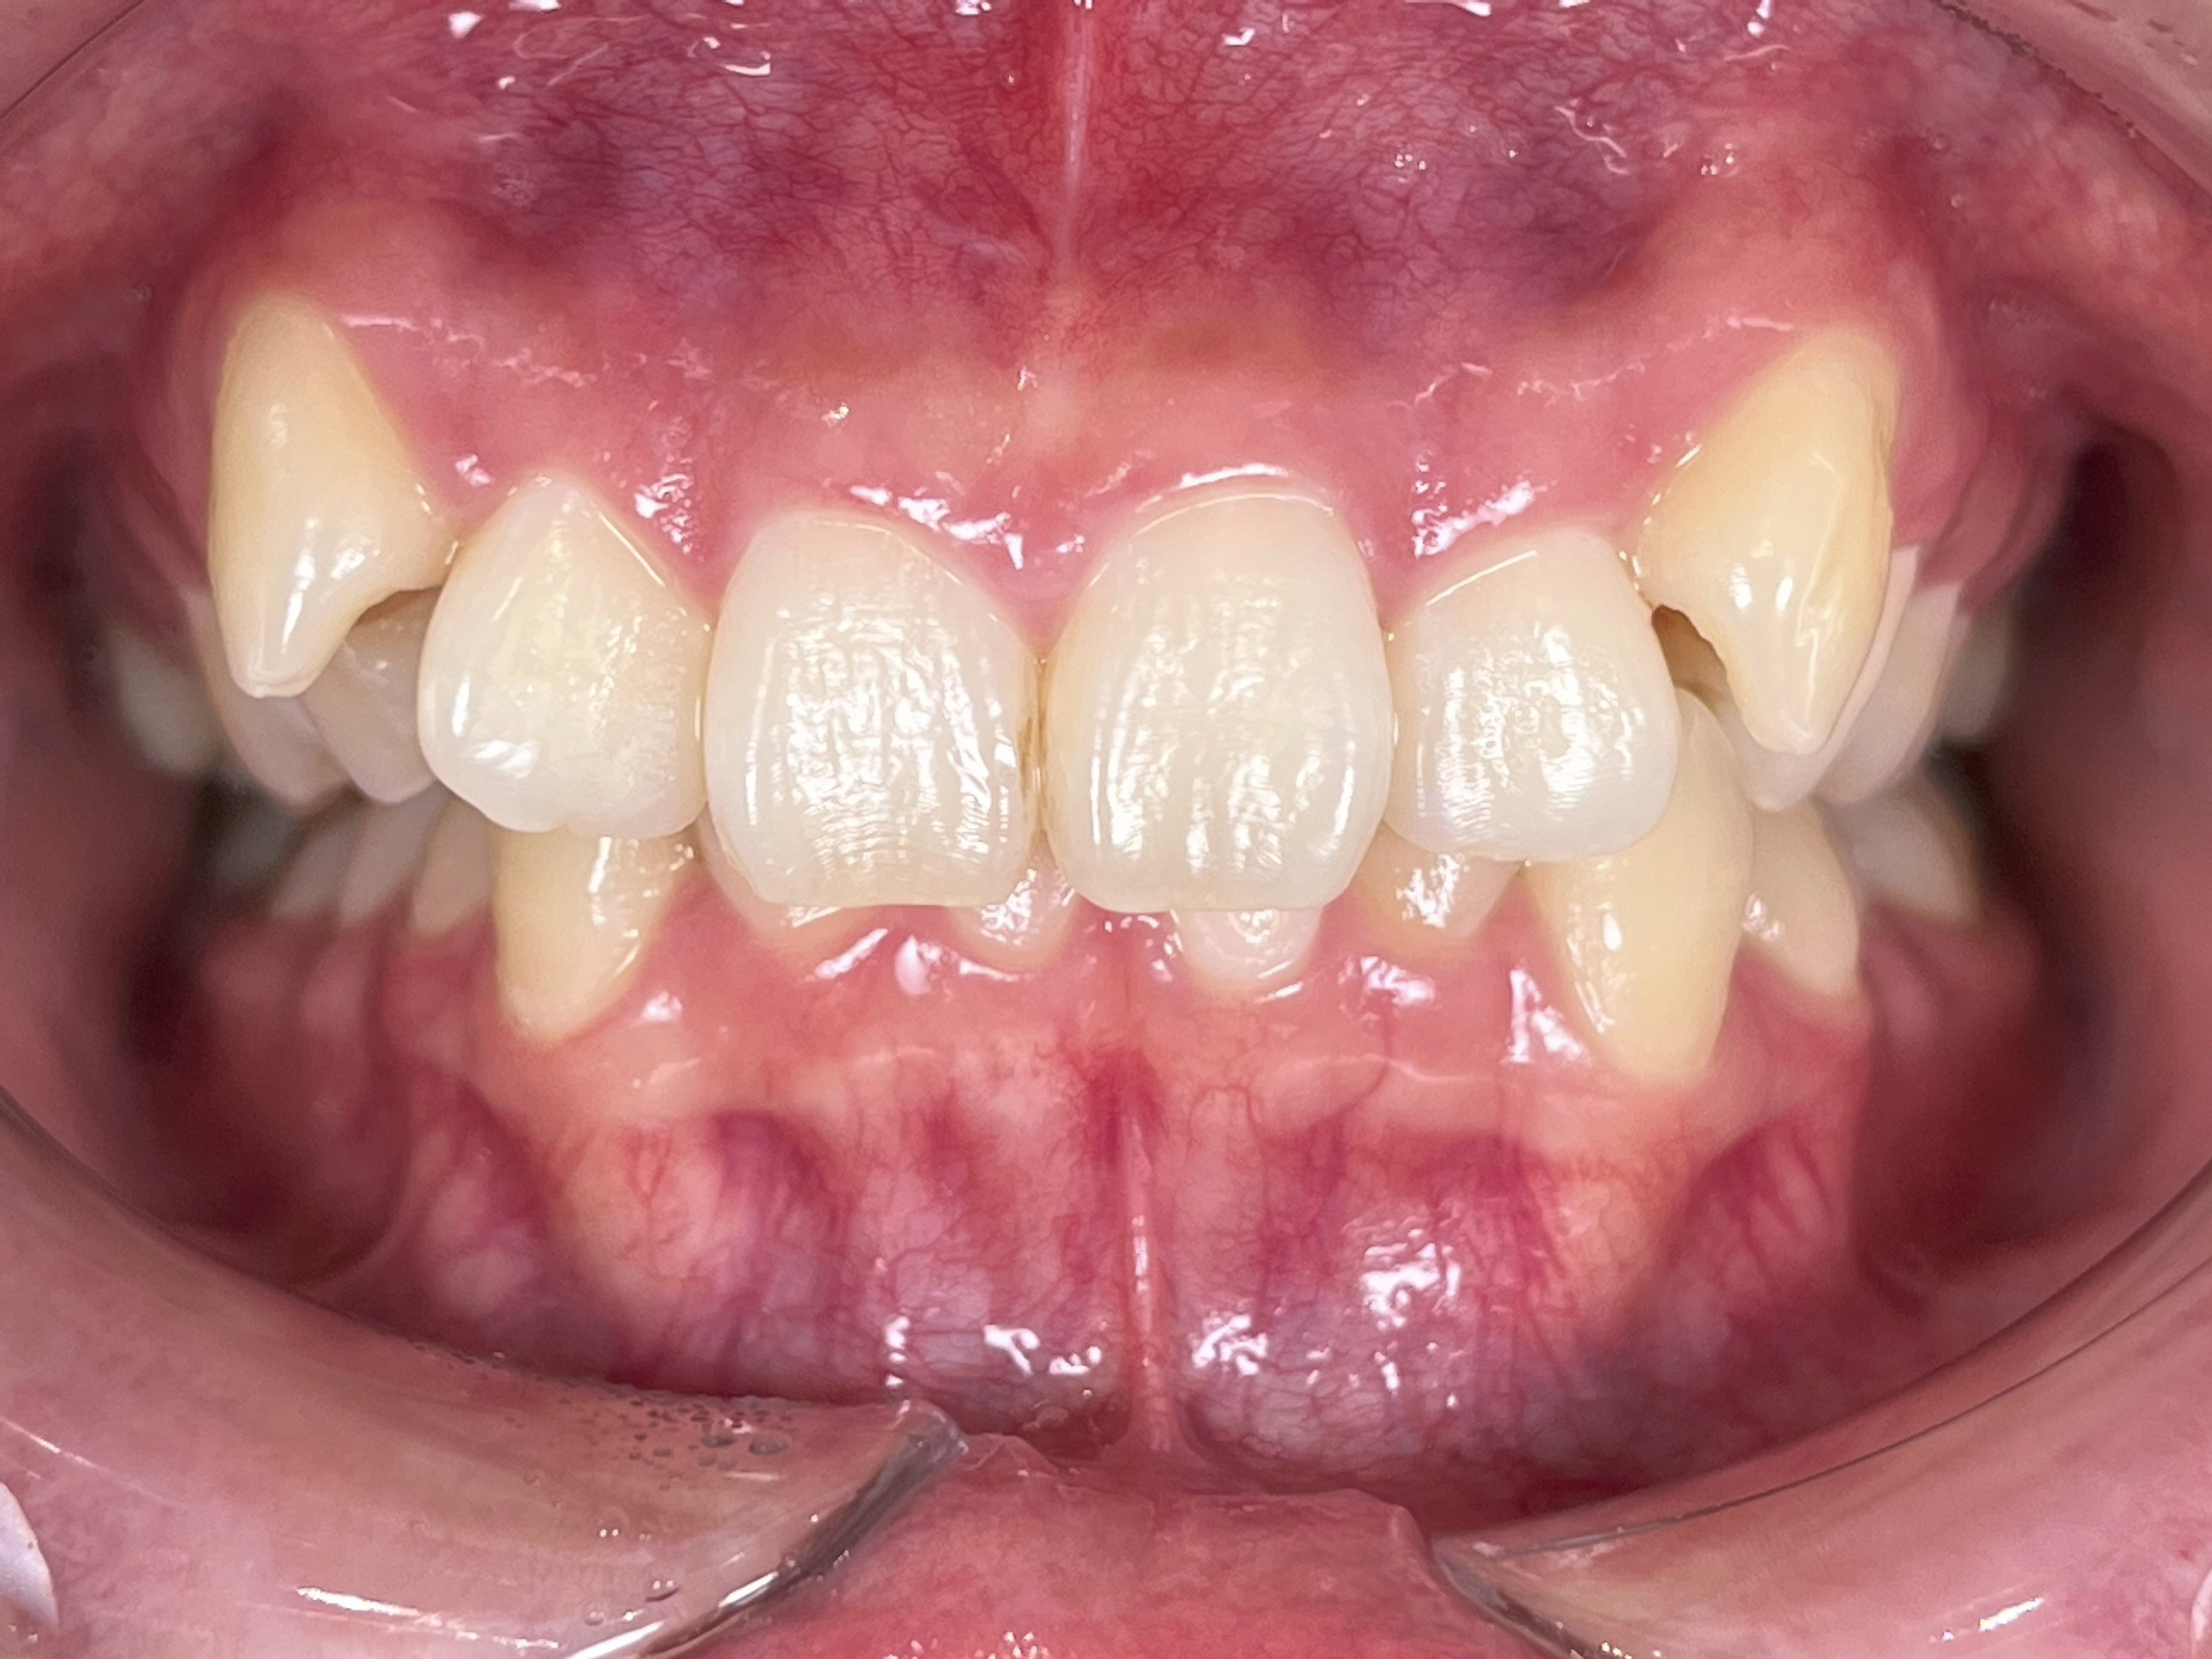

Before

(治療前)

患者様情報 23歳 女性 診断名 上顎前突、叢生(そうせい) 治療内容 マウスピース矯正(クリアコレクト) 期間・通院回数 約18か月 / 20回 費用(総額) 857,000円(税込) リスク・副作用 治療の初期段階では痛みや不快感が生じやすくなりますが、通常1週間前後で慣れていきます。 マウスピース矯正の症例 2